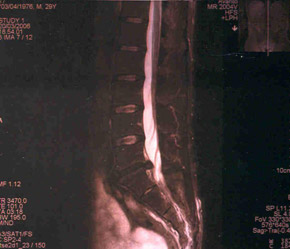

Immagine di un prolasso discale tramite RMN.

La freccia indica l’accumulo posteriore di materiale discale che deborda dalle limitanti vertebrali, scollando il legamento longitudinale posteriore.